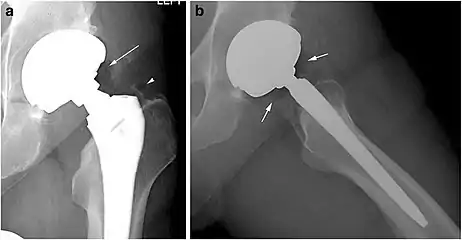

Joints

Pneumarthrosis is the presence of air in a joint. Its presentation on radiography is a radiolucent cleft often called a vacuum phenomenon, or vacuum sign.[7] Pneumarthrosis is associated with osteoarthritis and spondylosis.[8]

Pneumarthrosis is a common normal finding in shoulders[7] as well as in sternoclavicular joints.[9] It is believed to be a cause of the sounds of joint cracking.[8] It is also a common normal post-operative finding at least after spinal surgery.[10] Pneumarthrosis is extremely rare in conjunction with fluid or pus in a joint, and its presence can therefore practically exclude infection.[8]

X-ray of a hip with hip replacement and pneumarthrosis, in this case aseptic.

X-ray of a hip with hip replacement and pneumarthrosis, in this case aseptic. A vacuum sign, or vacuum phenomenon, is a normal finding on shoulder X-rays.

A vacuum sign, or vacuum phenomenon, is a normal finding on shoulder X-rays.